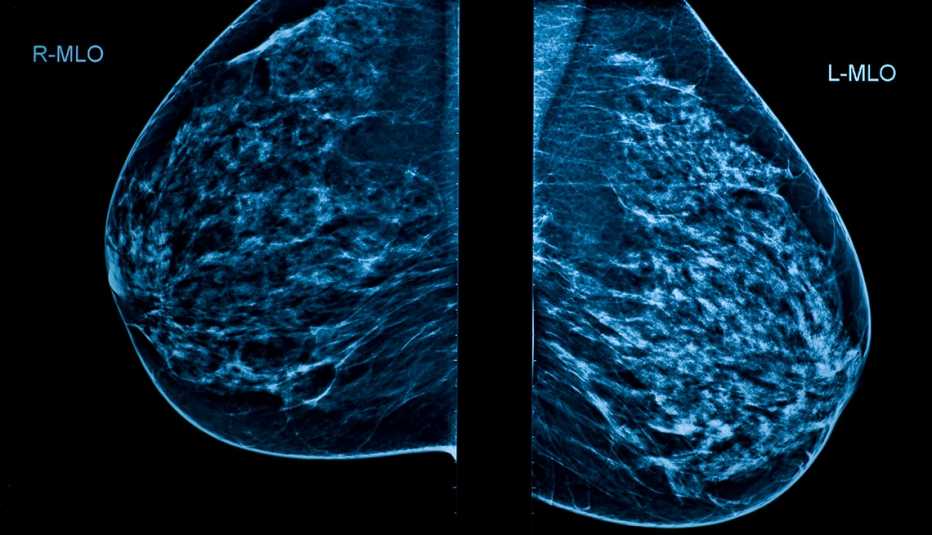

El diputat de Compromís i portaveu de Sanitat, Carles Esteve, ha denunciat hui en roda de premsa a Les Corts la gravíssima situació del servei de radiologia pública a la Comunitat Valenciana, amb endarreriments en mamografies i ecografies que afecten especialment el diagnòstic precoç del càncer.

Esteve ha anunciat este matí que Compromís acaba de guanyar una sentència davant el Tribunal Superior de Justícia de la Comunitat Valenciana (TSJCV) que obliga la Conselleria de Sanitat a lliurar les factures de totes les derivacions de radiologia, incloent mamografies, ecografies, ressonàncies i TACs. Esta sentència és el resultat dels recursos a la justícia per la negativa de la Conselleria a donar cap informació oficial a l’oposició sobre la situació de la radiologia. “La situació que s’està destapant ara, amb dades provisionals que parlen de 12.000 mamografies menys que l’any anterior, només és la punta de l’iceberg. El PP amaga informació perquè el model que impulsa no només falla, sinó que genera incerteses dramàtiques i mata”, ha afirmat Esteve.

El diputat ha compartit dues històries personals que li han arribat directament que il·lustren la gravetat del problema. En el primer cas, una dona del programa de cribatge no va rebre la seua citació el 2024 ni el 2025; va pagar a una clínica privada i li van detectar un càncer de mama. Ara es tracta a la pública, que respon bé una vegada fet el diagnòstic, però “no es pot permetre este calvari fins el diagnòstic”. El segon cas amplia el focus: una dona que anà al metge amb mal de pit va haver d’esperar un mes per a la mamografia, que donà resultat negatiu. Com continuava fent-li mal, setmanes després li realitzen una biòpsia i una ressonància, de la que no li donen el resultat; la metgessa de capçalera li diu que espere 15 dies a què arriben. Va acabar sabent del seu càncer a urgències on anà perquè continuava fent-li molt de mal el pit, i on van comprovar, al sistema, que el diagnòstic ja estava fet dues setmanes abans. “Estos no són casos aïllats; són la conseqüència d’un sistema que expulsa professionals i retalla recursos públics”.